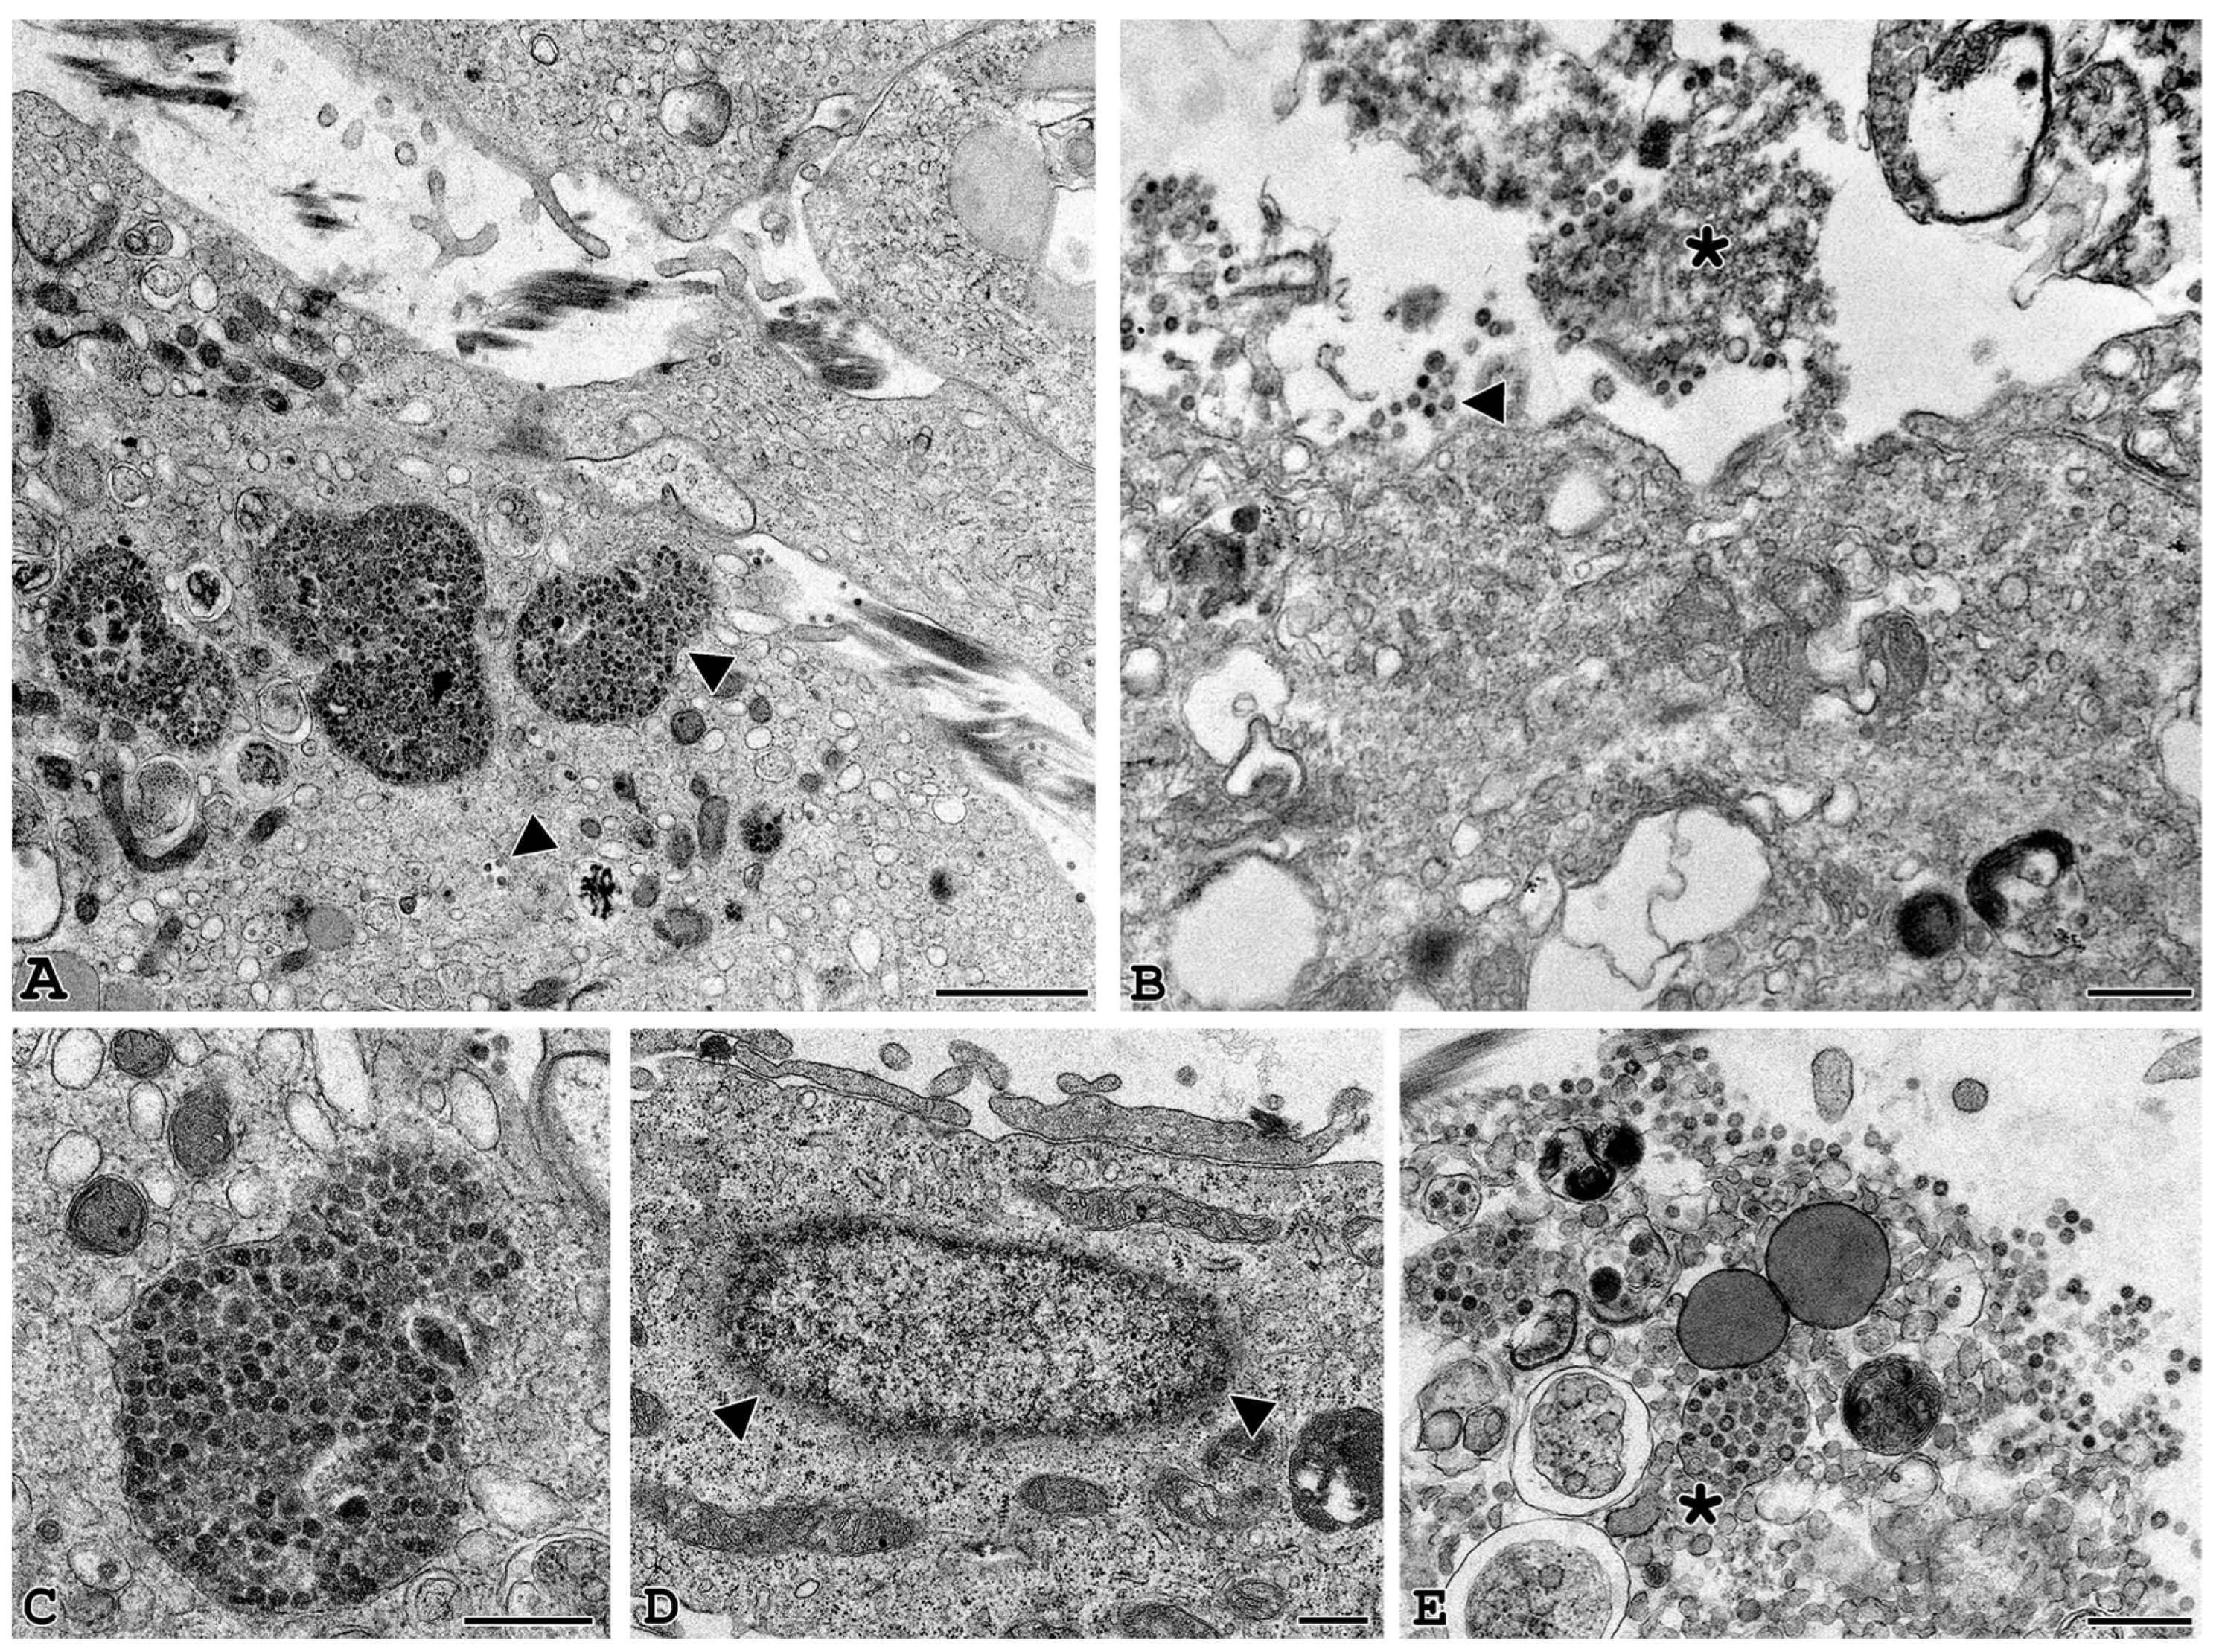

3.3. Electron Microscopy Identification of SARS-CoV-2